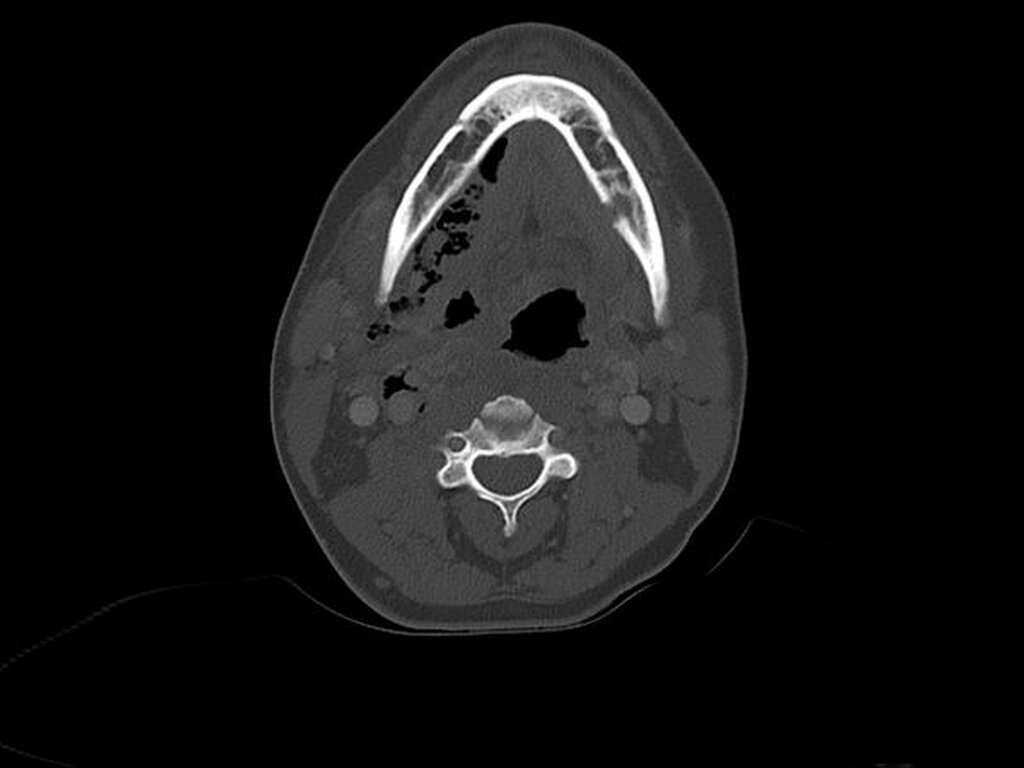

Bei der klinischen Untersuchung zeigte sich eine teigige, schwer abgrenzbare Schwellung submental und submandibulär beidseits, die bis zur Clavicula reichte (Abbildung 1). Weiterhin war ein deutliches Luftemphysem tastbar. Die Mundöffnung war eingeschränkt, die Uvula im Sinne des Kulissenphänomens nach rechts verlagert und der Mundboden schwellungsbedingt angehoben. In der OPG-Aufnahme zeigte sich ein Zustand nach Entfernung des Zahnes 36 mit einliegender Tamponade (Abbildung 2). Aufgrund des ausgedehnten Befunds mit reduziertem Allgemeinzustand wurde zusätzlich eine Computertomografie durchgeführt. Dabei war neben der ausgedehnten Flüssigkeitsansammlung beidseits im Bereich des Mundbodens eine ausgedehnte phlegmonöse Entzündungsreaktion parapharyngeal und paralaryngeal entlang der Gefäß-Nervenstraße bis ins obere Mediastinum sichtbar (Abbildung 3). Zusätzlich waren beidseits erhebliche Lufteinschlüsse vom Mundboden über die Halsweichteile bis ins Mediastinum erkennbar. Im Laborbefund zeigten sich deutlich erhöhte Entzündungswerte mit einem CRP von 56,2 mg/dl und Procalcitonin von 7,6 ng/ml.